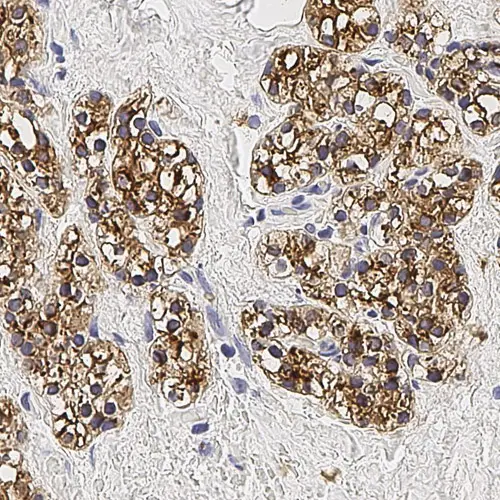

Human parathyroid adenoma: immunohistochemical staining for Parathyroid Hormone. Note membrane/cytoplasmic staining of tumor cells. Parathyroid Hormone: clone 105G7

L'hormone parathyroïdienne est le régulateur principal des taux sanguins de calcium. Les cellules principales sont les cellules les plus abondantes dans la glande parathyroïde, et sont responsables de la sécrétion de l'hormone parathyroïdienne. Les anticorps anti-hormone parathyroïdienne, utilisés en conjonction avec des anticorps anti-thyroglobuline, sont utiles pour distinguer les lésions dérivées de la parathyroïde des lésions dérivées de la thyroïde.